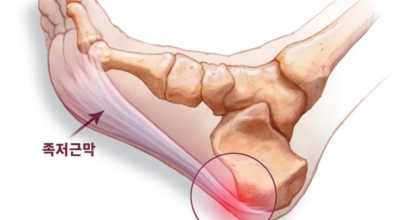

족저 근막염이란?

족저 근막이란 발가락 시작지점부터 발뒤꿈치뼈까지 발바닥 전체를 감싸고 있는 두꺼운 막을 말해요. 족저 근막은 발바닥 아치를 보존시켜 발바닥이 지면을 내딛음으로써 생기는 쇼크을 흡수하는 중요시되는 역할을 수행하고 있어요. 이 족저 근막에 일차적으로 서서히 조직 훼손이 일어나고 계속적인 활동에 의하여 염증이 커지면서 발 뒤꿈치 부근 통증을 일으키게 되는데 염증은 무리하고 반복적인 동작, 많은 활용으로 마찰에 의해 발생해요.

족저 근막염은 염증에 의한 훼손 및 통증을 유발하는 질환인데요 족저 근막염 증상은 동일한 발뒤꿈치 통증 하글런드 병변의 기형으로 알려져 있으고 아킬레스 건과 연관이 깊다고 해요. 특히 근육이 덜 풀린 아침 시간 대는 보행 시 날카롭고 바늘로 찌르는 듯한 심한 통증을 느끼게 된다고 해요. 하지만 아침 시간 대를 지나 오후에 접어들면서 일정 양 통증은 서서히 감소하기 시작한다고 하는데요 초기 증상이 나타난다면 필수로 전문의를 찾아 조기치료하는 것이 바람직해요.